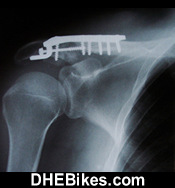

Another shot post surgery photo showing Downhill Dave's right shoulder with the titanium hardware.

This is the after-surgery x-ray of Downhill Dave's right shoulder.

The titanium hardware consists of 6 bolts/ screws and the one big plate.

About a year after the surgery, I actually had to have another surgery to remove the titanium as it was binding in my shoulder and causing extreme pain.